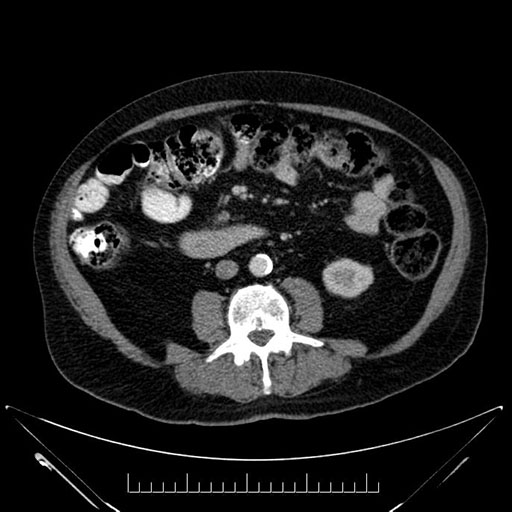

Imaging Analysis

Look through the patient's CT scan to identify any areas of concern for the necessary procedure.

Based on your CT findings, which issue(s) would give reason for "planned slowing down moment(s)" in this case?